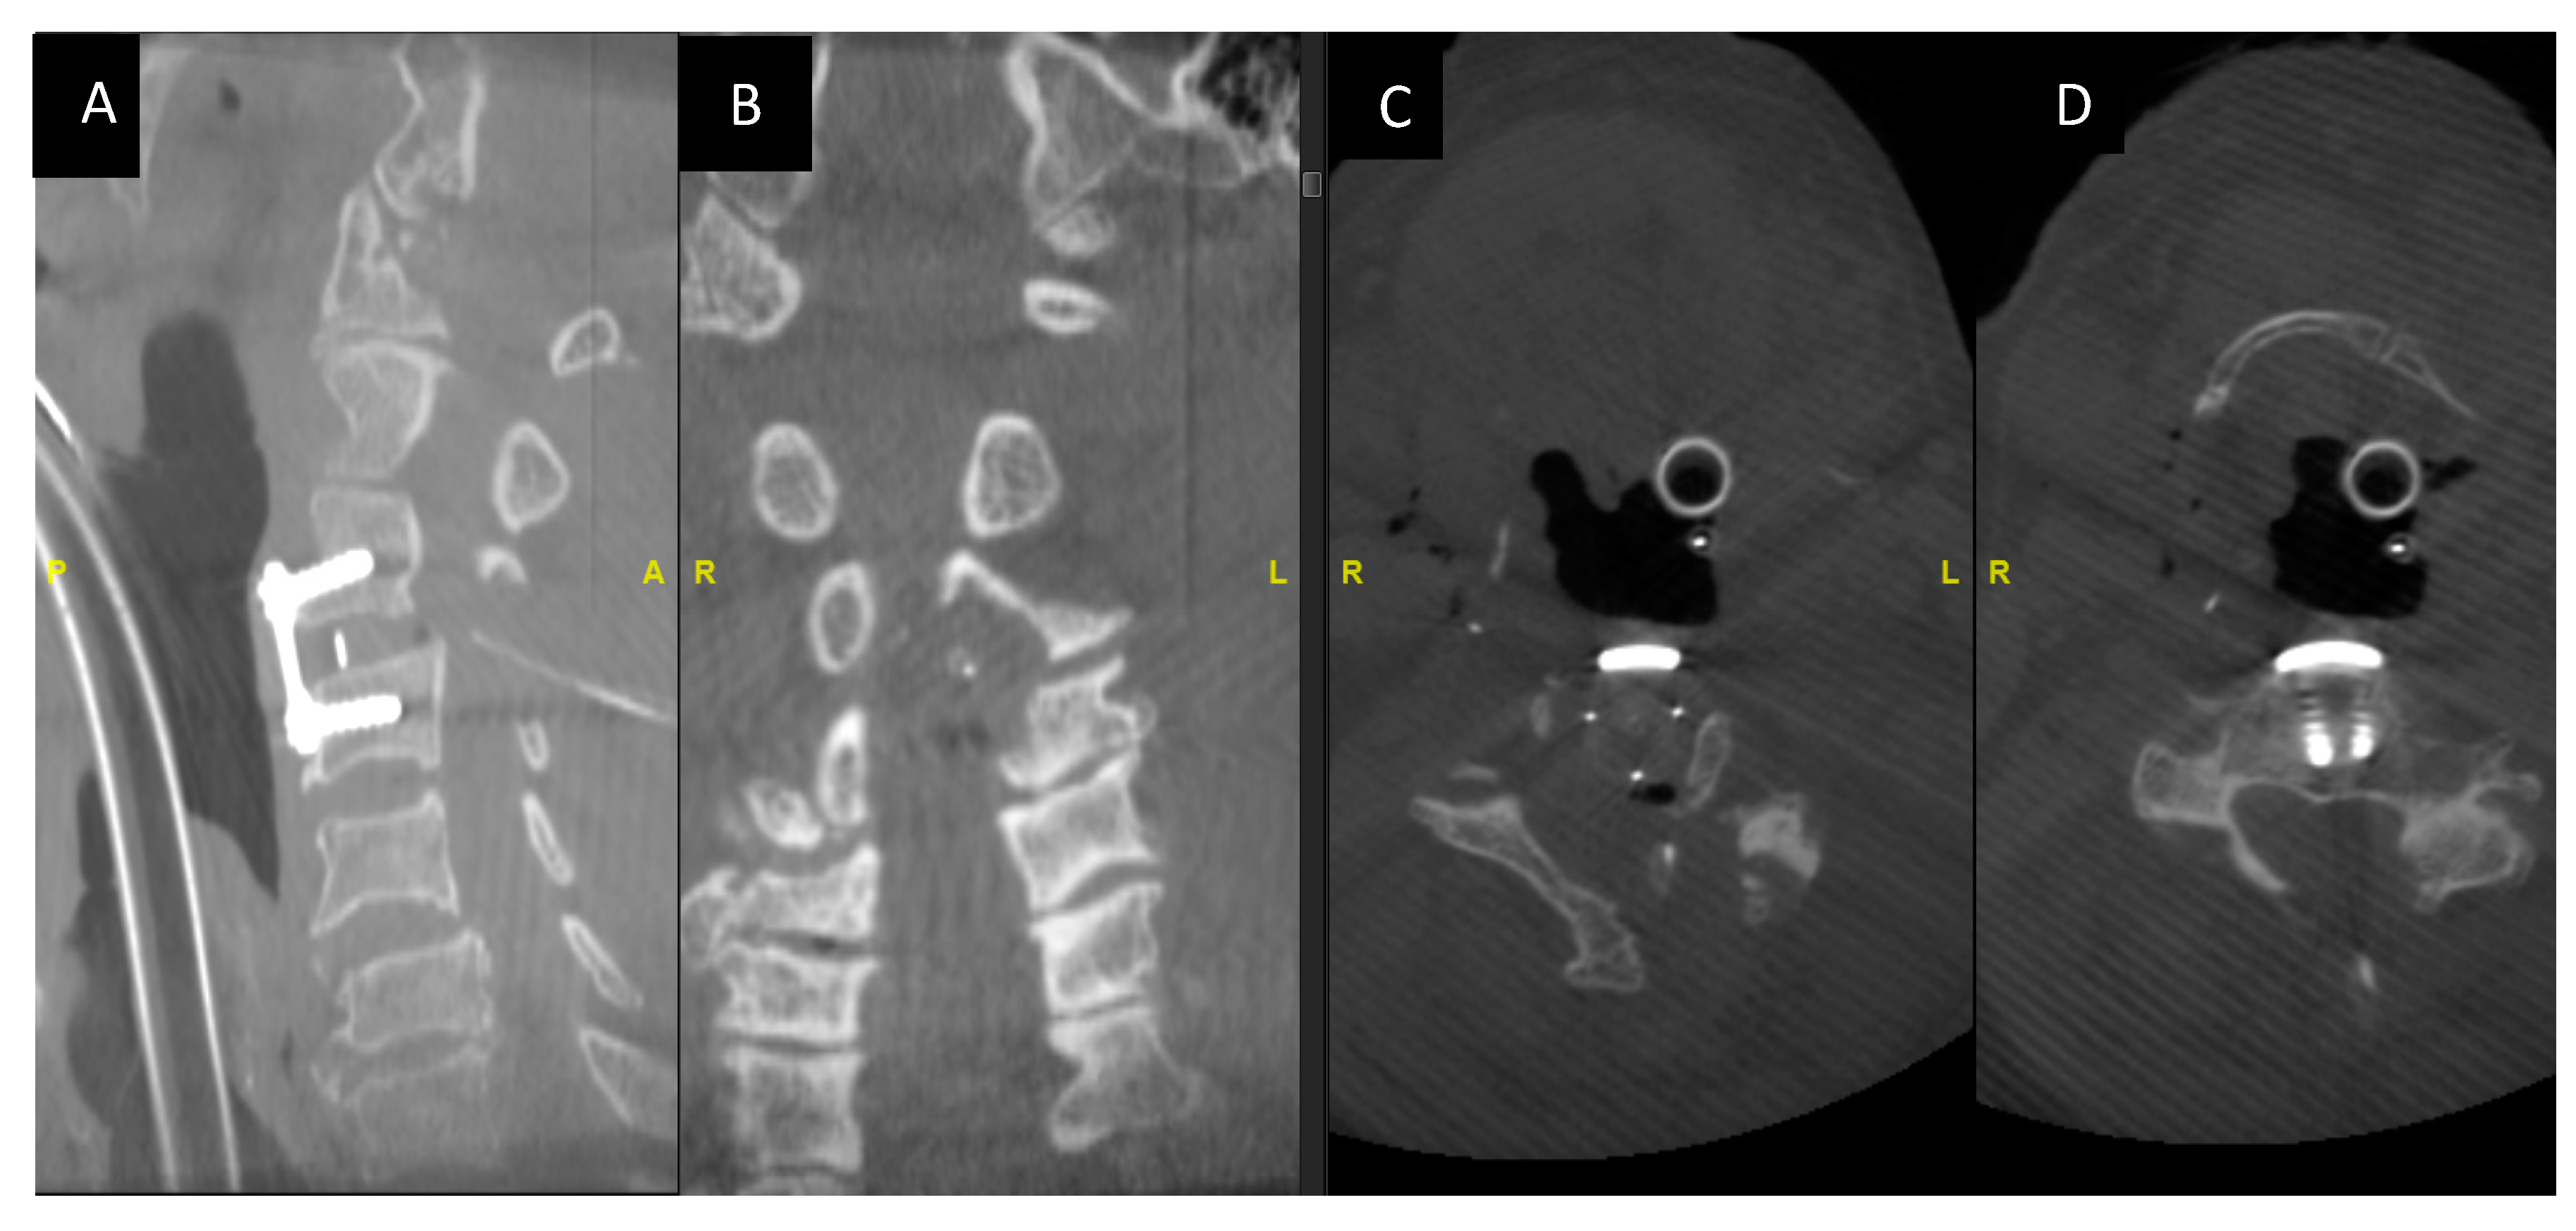

2.9. Confirmation of Decompression Using Intraoperative Computer Tomographic (O Arm) SCAN

After the completion of decompression, we perform an intraoperative 3-D CT imaging using an O- Arm to radiologically confirm the adequacy of decompression (Figure 6A–D).

Figure 6.

Intraoperative O-arm CT images showing the adequacy of decompression and the implant position. (A,B) Intraoperative O arm imaging sagittal and coronal images post-decompression. (C,D) Axial cuts at the C3 level post-decompression.